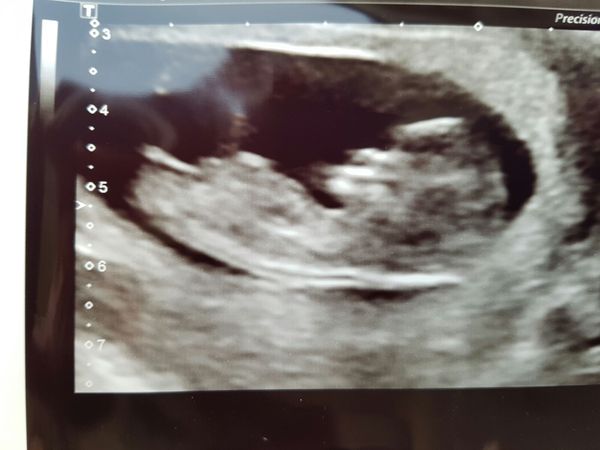

Keeping my 20wscan is on 27th sept, I'll be 20+3.